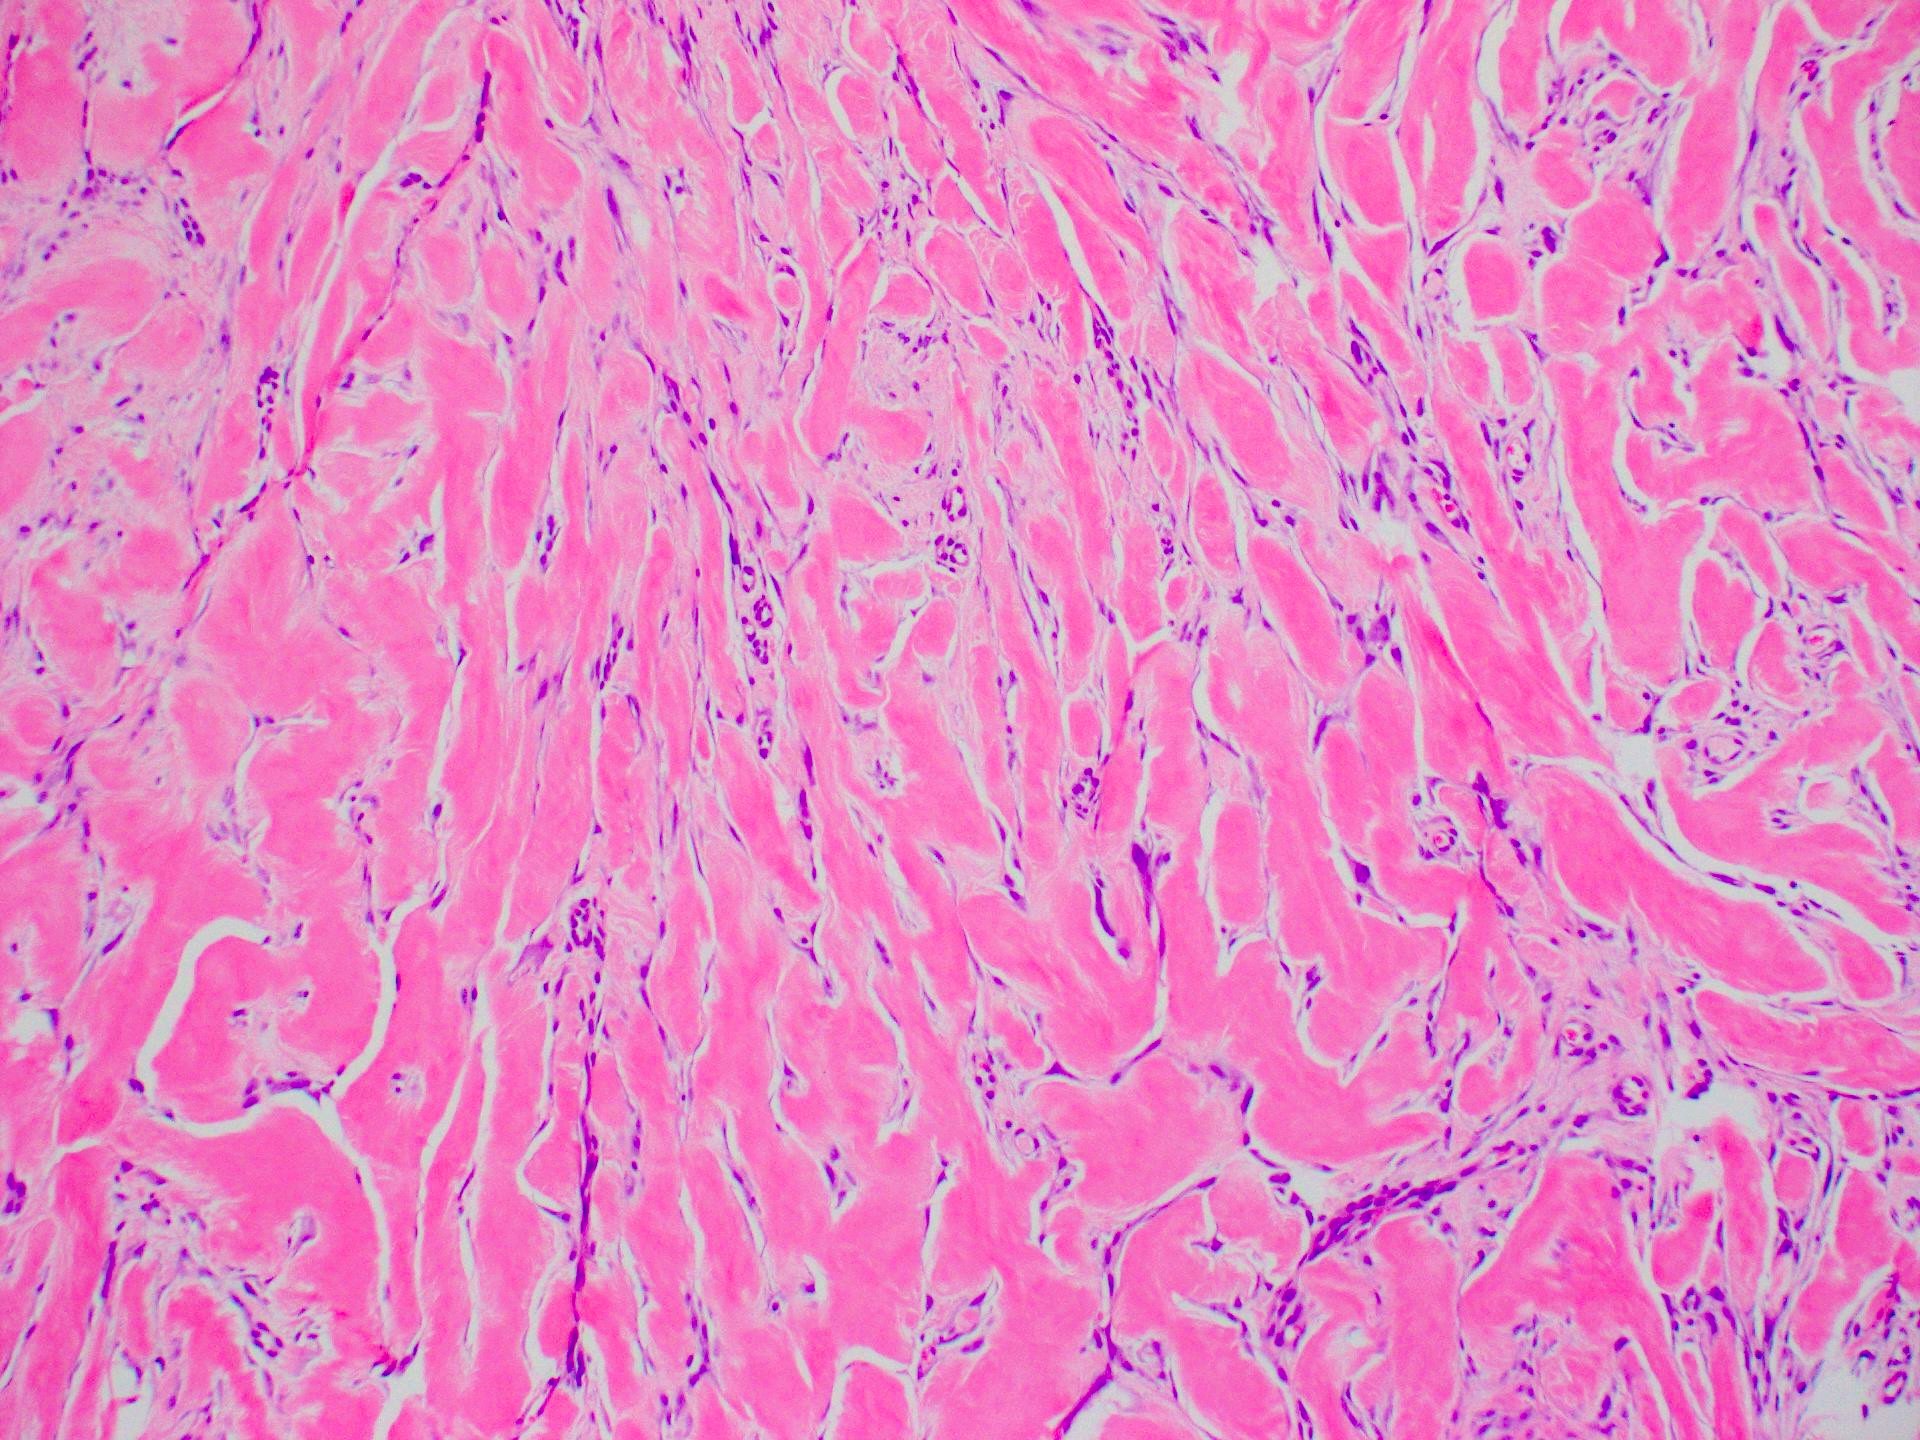

Microscopic (histologic) description

- Lesion of the deep dermis; sparing of papillary dermis (Am J Dermatopathol 2004;26:379)

- Characteristic long, broad, closely packed collagen bundles that stain uniformly eosinophilic (keloidal collagen) arranged in haphazard fascicles (Scars Burn Heal 2021;7:2059513120980320)

- Fibroblasts are increased compared to normal skin (Front Cell Dev Biol 2020;8:360)

- May appear edematous due to increased dermal mucosubstances (J Zhejiang Univ Sci B 2022;23:699)

- Tongue-like advancing edge (Front Cell Dev Biol 2020;8:360)

- Epidermis may be normal, thin or thick (most) and may be affected by secondary changes (such as hypertrophy and inflammation due to irritation / scratching) (Front Cell Dev Biol 2020;8:360)

- Lesion replaces adnexal structures (i.e., hair follicles and sweat glands) (Histol Histopathol 2015;30:1033)

- Fewer capillaries and blood vessels than surrounding skin (J Plast Surg Hand Surg 2010;44:272)

- Tend to have marked inflammation in the dermis at the leading edge of growing keloids (Scars Burn Heal 2021;7:2059513120980320)

- Overlap with hypertrophic scar and therefore correlation with the clinical features is recommended

Microscopic (histologic) images

Board review style answer #2

C. Keloid. The image shows the classic and characteristic appearance of keloidal collagen. Answer A is incorrect because while dermatofibroma can be similar in appearance, it is typically more cellular and is most common on the legs. Answer B is incorrect because while hypertrophic scars can overlap in histological appearance with keloid, they are generally more cellular and have less keloidal collagen. Clinical history helps to make the diagnosis as Asian individuals have a much higher risk, keloids are most common in young people (10 - 30 years old) and the earlobe is a typical site. Answer D is incorrect because while scleroderma / morphea can mimic keloid on a small biopsy, the collagen pattern is different (being more ordered and almost acellular) and the clinical history is not suggestive.